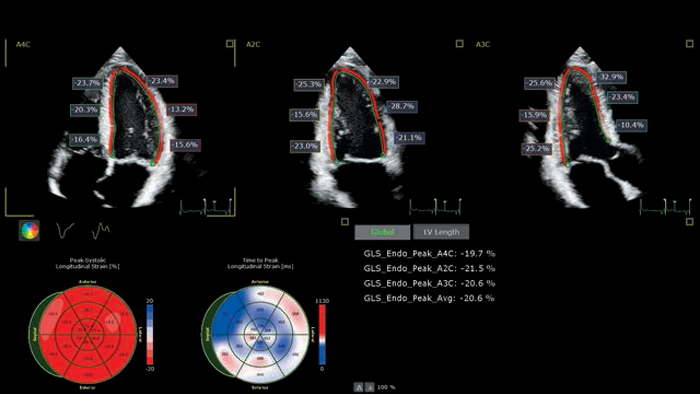

The EPIQ CVx is a dedicated cardiac ultrasound solution which brings significant advancements in functionality. This helps you deliver better care through higher processing power, exceptional imaging with more clarity & sharpness, improved exam efficiencies, complemented by the proven, robust quantification capabilities of Ultrasound Workspace.

Cardiac imaging modalities support a more confident stratification of cardiovascular toxicity while serving as a powerful baseline reference for treatment and long-term follow-up.